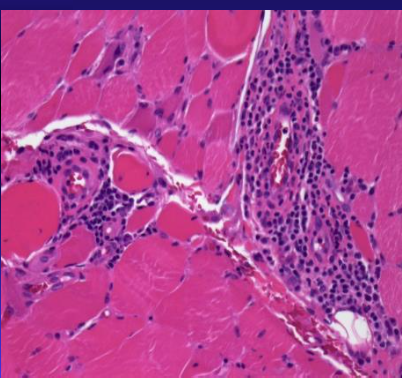

pathology in polymyositis

cytotoxic CD8+ T lympocytes in muscle fibers - these express CD45RO

ICAM-1 expressed in muscle fibers

endomysial inflammation w/ predominantly CD8 T cells in polymyositis

pathology of dermatomyositis

perimysial inflammation w/ CD4+ T cells

complement deposited of vessels

perimysial inflammation w/ CD4 T cells in dermatomyositis

describe pathologic differences b/t polymyositis and dermatomyositis